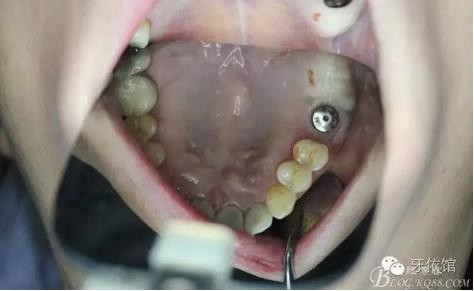

術后6個月口內(nèi)照

右上7上愈合基臺